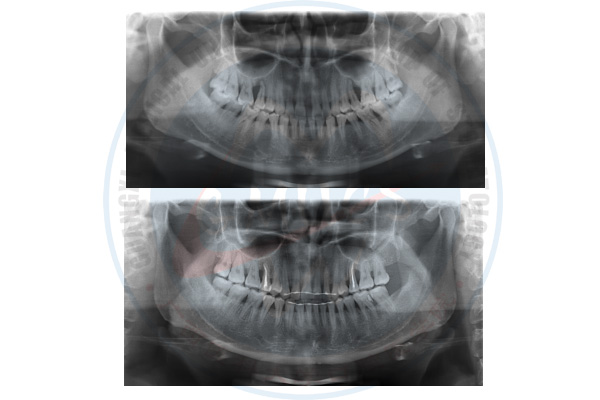

正畸-牙周-牙体牙髓联合治疗前后曲面断层片对比